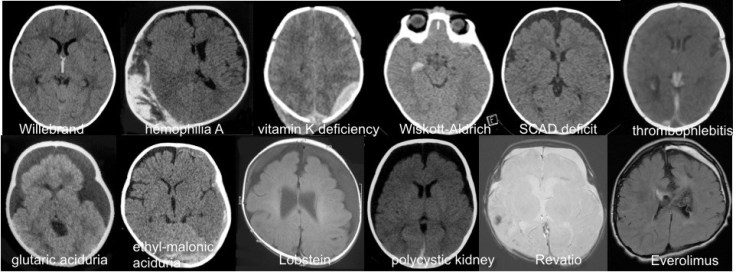

il existe de plus de multiples pathologies rares voire très rares qui sont des diagnostics différentiels des hématomes traumatiques :

le diagnostic est fait aisément :

- sur le bilan standard

- sur les antécédents de l’enfant et le contexte syndromique

- sur les particularités radiologiques du saignement